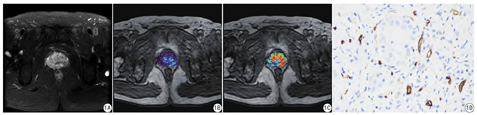

前列腺癌区、中央腺体增生区及外周带非癌区的Ktrans、Kep值的差异有统计学意义(P <0.05),见 表1、图1。Ktrans、Kep值对早期前列腺癌的诊断效能中等,见表2。

前列腺癌标本均行免疫组化MVD测定。MVD计数方法:以棕黄色染色的内皮细胞或内皮细胞簇作为单个可计数的微血管。首先在低倍镜(×40)下观察全片,找出3个微血管着色最密集的区域,然后在高倍镜(×400)下观察,记录3个视野中的微血管数,计算其平均值作为MVD,表示为微血管数/视野。